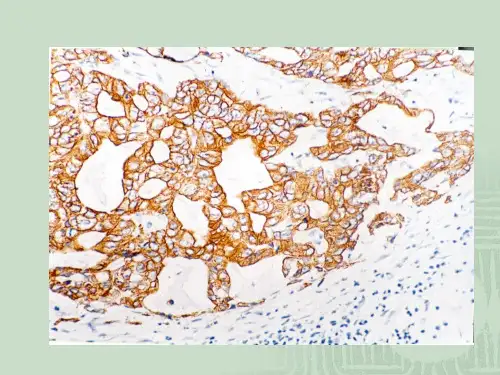

在免疫组化最后结果的判断时,常可见到均匀一片的似非特异性染色的现象,经多方研究认为,它是一种假性非特异性的染色。

因为肿瘤组织中含有的抗原较易发生扩散弥散,肿瘤细胞无限制的生长和生长过速,导致肿瘤中间部分组织血液供给困难,造成缺血坏死,坏死细胞中的抗原由于机体的作用,可以被均匀地散布于细胞与细胞间的间质,这是抗原发生弥散的一种方式。

另一种抗原弥散的方式就是,由于组织没有及时的固定所引起的。

离体的组织不及时固定,组织就会自溶,抗原就会扩散,这是一非常普通的常识,但要做好却是极不容易。